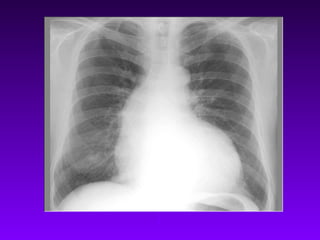

• Apare hipertensiune arteriala pulmonara,

care duce la hipertrofia si dilatarea

ventriculului drept.

• Staza pulmonara: - dispnee de efort,

dispnee paroxistica nocturna, ortopnee,

edem pulmonar acut